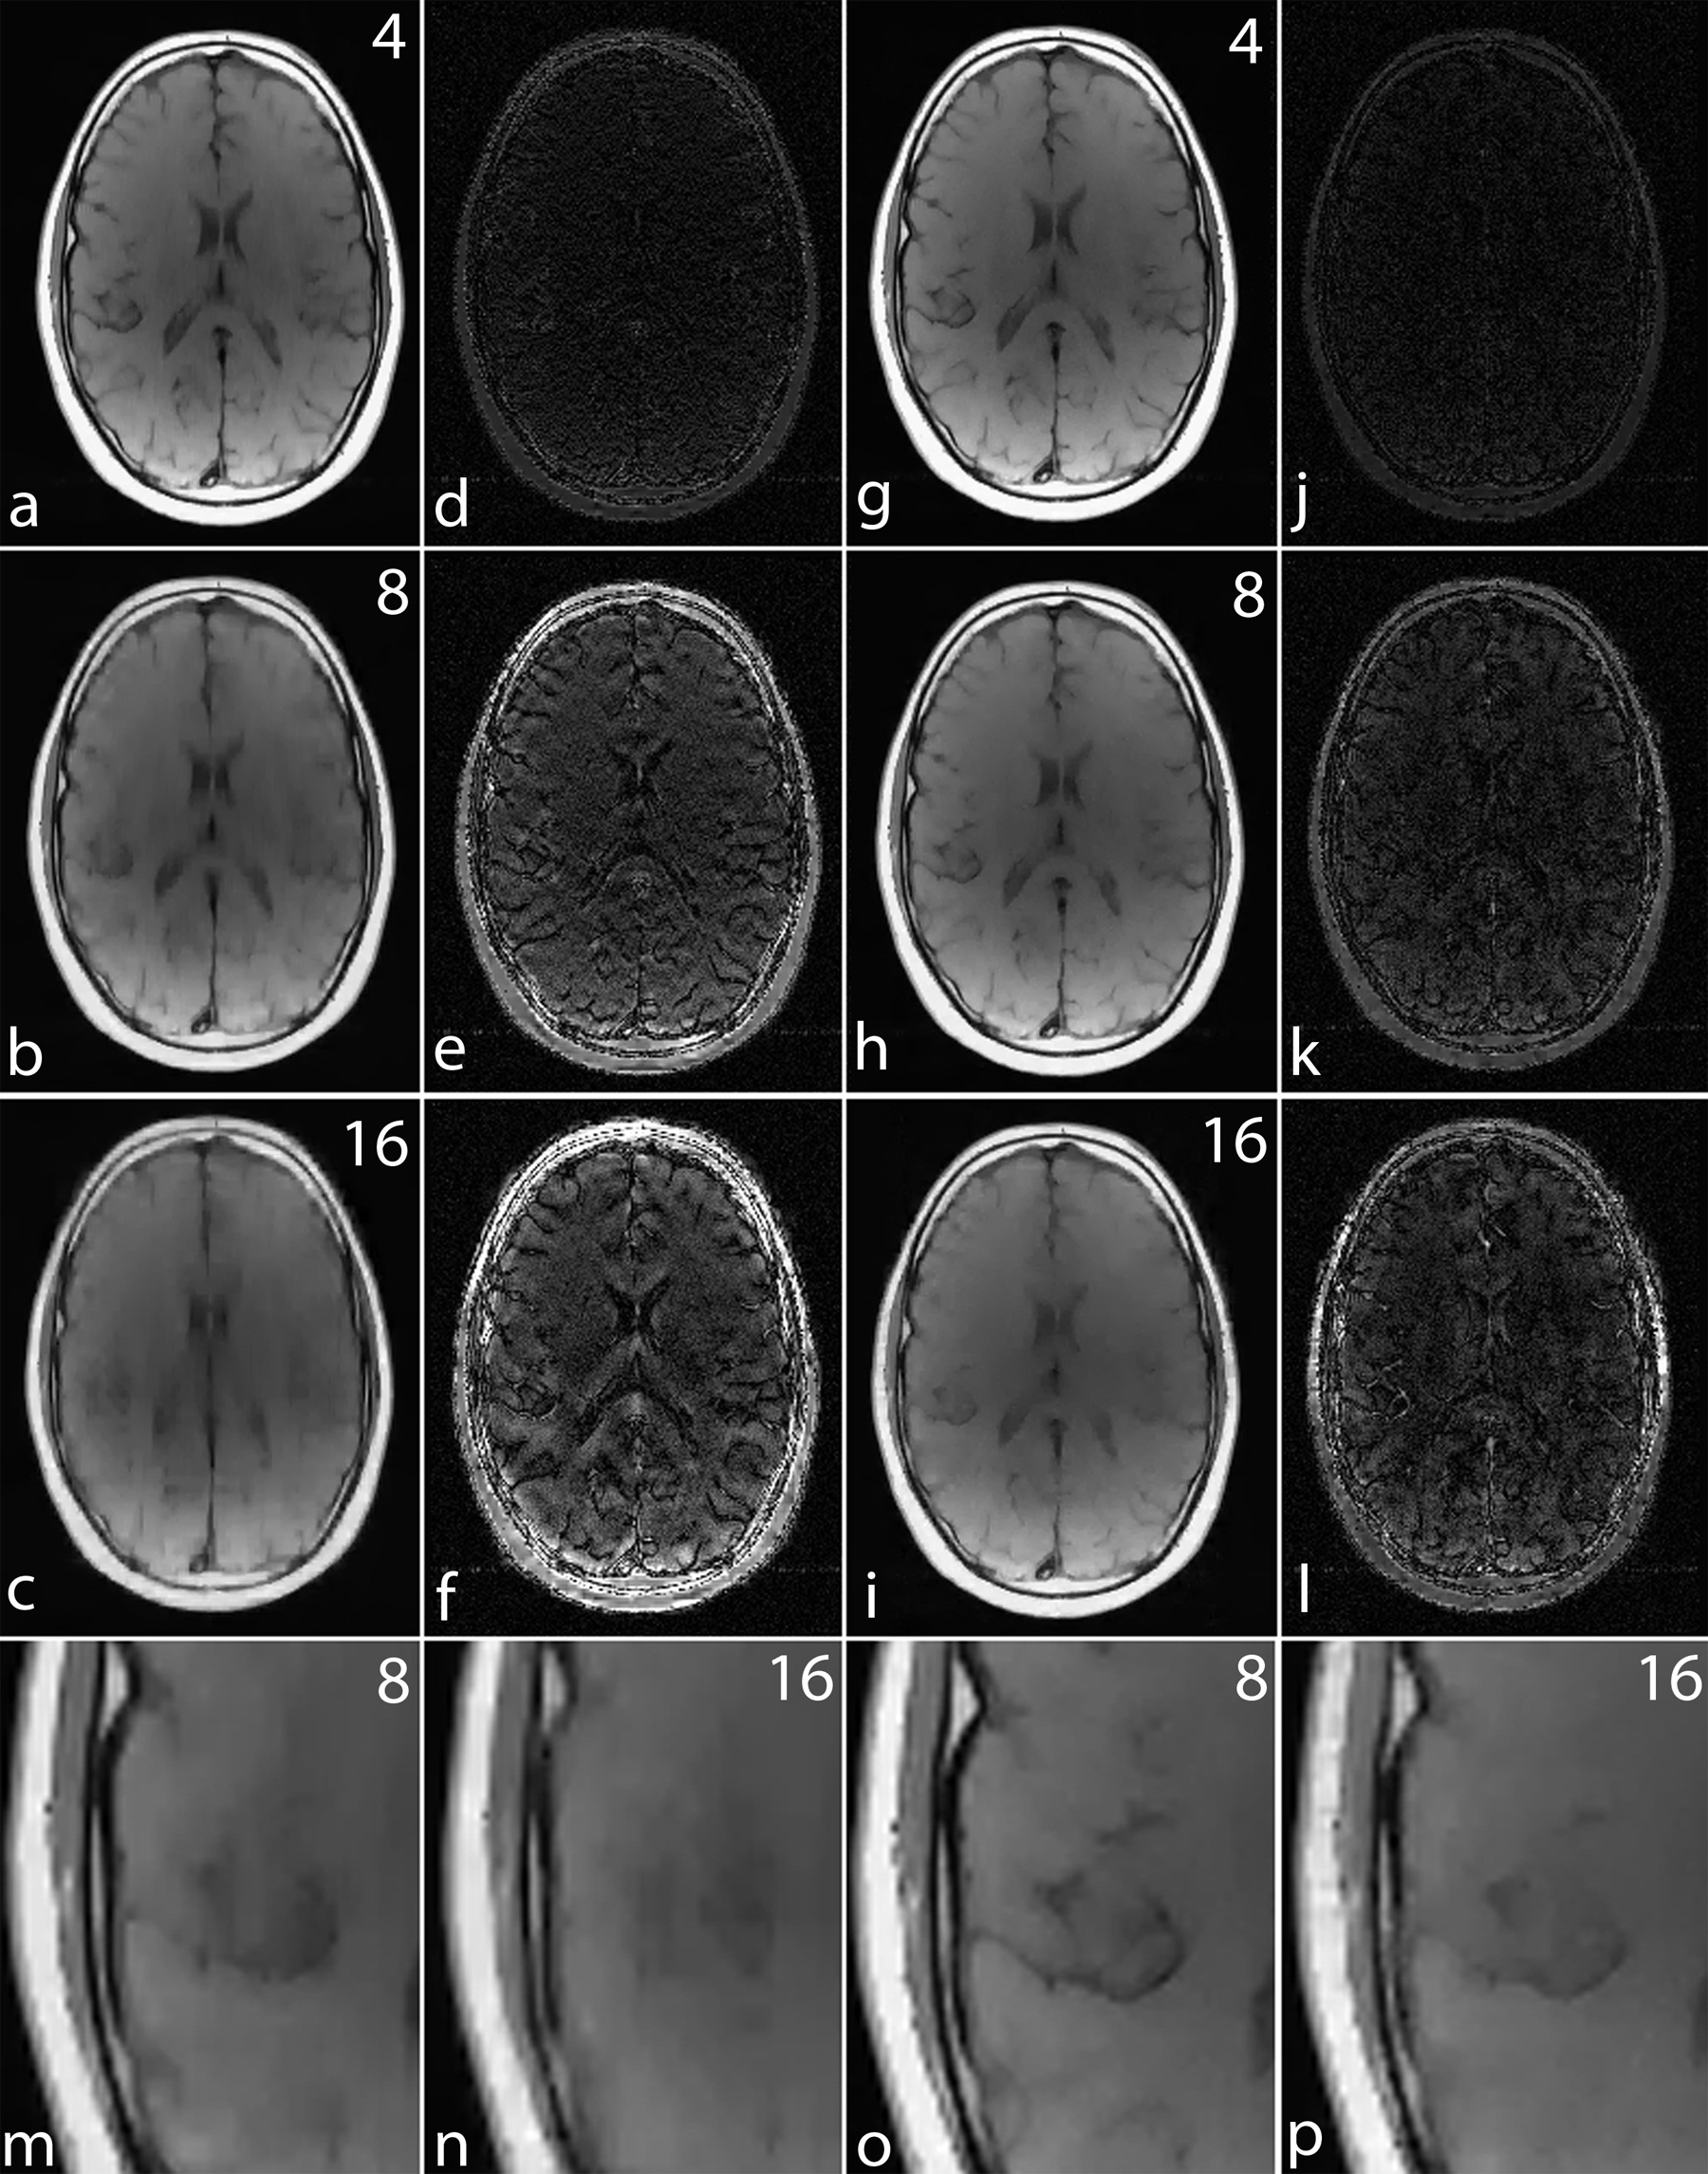

Refer to caption

Figure 8: Simulation results for MCS-MRI comparing the noiselet encoding and Fourier encoding schemes (up/down: phase encodes, left/right: frequency encode). (a)-(c): show images reconstructed with Fourier encoding for acceleration factors of 4, 8, and 16 respectively; (d)-(f): show difference images with Fourier encoding for acceleration factors of 4, 8, and 16 respectively; (g)-(i): show images reconstructed with noiselet encoding for acceleration factors of 4, 8, and 16 respectively; (j)-(l): show difference images with noiselet encoding for acceleration factors of 4, 8, and 16 respectively; (m)-(n): show zoomed portion of images reconstructed with Fourier encoding for acceleration factors of 8, and 16 respectively; (o)-(p): show zoomed portion of images reconstructed with noiselet encoding for acceleration factors of 8, and 16 respectively. The zoomed images highlight that MCS-MRI using noiselet encoding reconstructions outperforms the Fourier encoding for preserving image resolution.

For a noiseless simulation, the reconstructed images for different acceleration factors (4, 8 and 16) are shown in Fig. 8. The difference images in Fig. 8 (d)-(f) and (j)-(l) demonstrate that the error in noiselet encoding is always less than in Fourier encoding, and that the noiselet encoded MCS-MRI reconstruction preserves spatial resolution better than the Fourier encoded MCS-MRI. Fig. 8 (m) and (n) show the zoomed images reconstructed with Fourier encoding for acceleration factors of 8 and 16 respectively, while Fig. 8 (o) and (p) show the zoomed images reconstructed with noiselet encoding for an acceleration factors of 8 and 16 respectively. The zoomed images highlight that the spatial resolution of the noiselet encoded reconstructions outperforms the Fourier encoded reconstructions. Moreover, the spatial resolution provided by the noiselet encoding at an acceleration factor of 16 is comparable to that of the Fourier encoding at an acceleration factor of 8, suggesting that noiselet encoding performs approximately twice as good as Fourier encoding.

To measure the relative error, simulations were performed on the brain image for 1000 times by randomly generating a sampling mask each time. The mean of the relative errors was calculated after 1000 such reconstructions at every acceleration factor. The mean relative error versus the number of measurements is plotted in Fig. 9 and highlights that noiselet encoding outperforms Fourier encoding for all acceleration factors. The relative error for noiselet encoding at an acceleration factor of 16 was the same as the relative error for Fourier encoding at an acceleration factor of 8 indicating that higher acceleration factors are achievable with noiselet encoding compared to Fourier encoding.